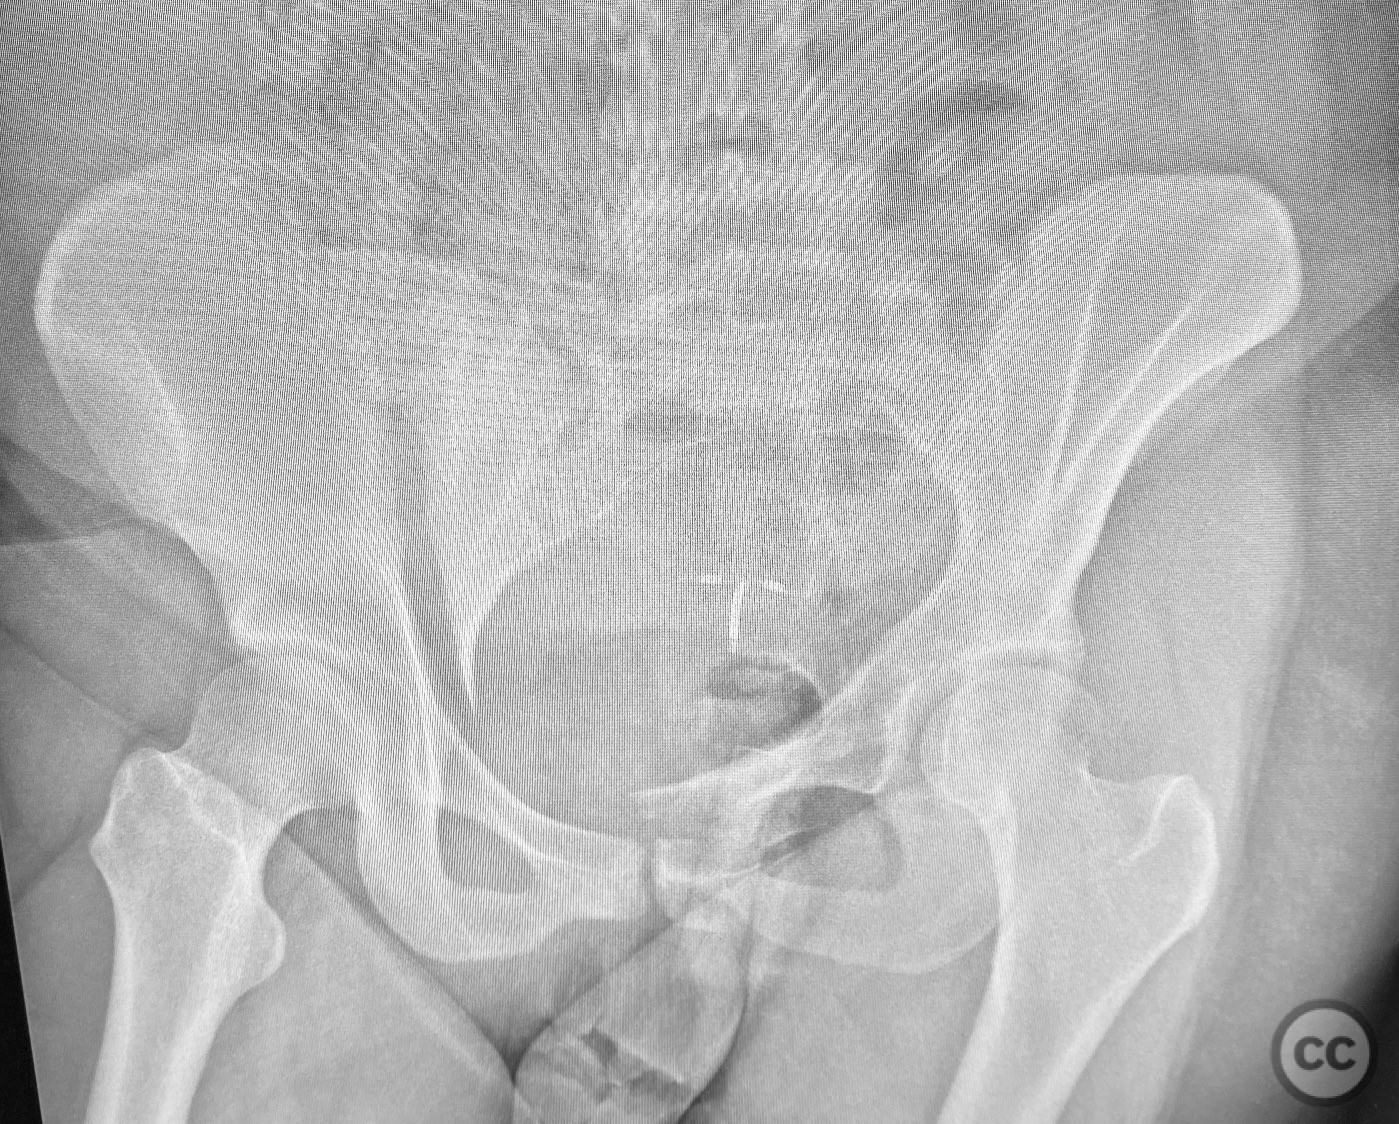

Clinical Details

Clinical and radiological findings:  The patient presented following trauma with an unusual, significantly displaced right iliac fracture, accompanied by left-sided sacral and parasymphyseal ramus fractures. Initial AP pelvic radiography demonstrated the complex injury pattern. CT imaging provided detailed characterization of the iliac and sacral fractures, including assessment of displacement, bone quality, soft tissue status, and overall body habitus. No neurovascular compromise was reported. AO/OTA classification: Right iliac fracture 61B2.3 (partial unstable, lateral compression injury), left sacral fracture Denis zone I, left parasymphyseal ramus fracture.